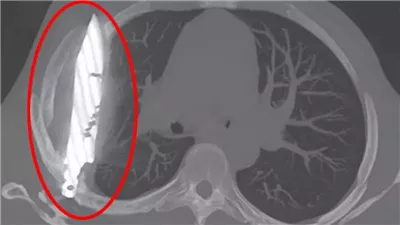

صدمة في تنزانيا رجل عاش بسكين في صدره لمدة 8 سنوات دون أن يدري